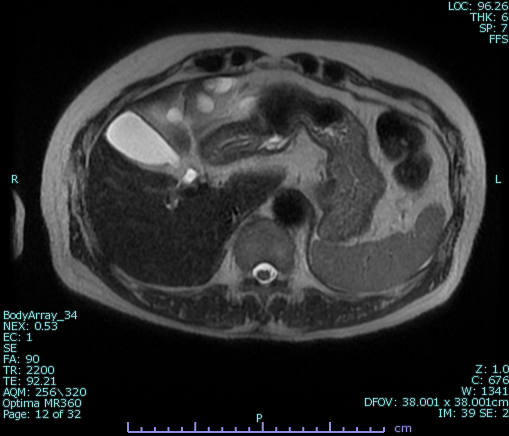

MRCPは、MRI(磁気共鳴画像)装置を使い、胆のう・胆管・膵管といった体内の“管”を詳しく調べる検査です。通常、こうした部分を詳しく調べるには内視鏡を使う必要がありましたが、MRCPは横になっているだけで、体に負担をかけずに詳しい画像を得ることができます。体への負担が少なく、安心して受けていただける検査のひとつです。

MRCPでは、主に次の3つの臓器の異常がないかチェックします。

● 膵臓(すいぞう)

膵石、膵管の拡張、膵管内乳頭粘液性腫瘍(IPMN)、膵臓がん など

特に膵臓は背中側に隠れているため、一般的な腹部エコーではガスの影響で見えにくいことがあります。

MRCPは磁気を利用するため体型やガスの影響を受けにくく、膵臓の異常の早期発見に優れています。